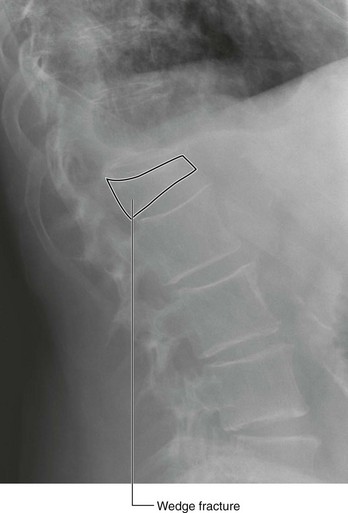

Osteoporosis is a disease in which the bone mineral density is significantly reduced. This renders the bone significantly more at risk of fracture. Typically, osteoporotic fractures occur in the femoral necks, the vertebra, and the wrist. Although osteoporosis may occur in men, especially elderly men, the typical patients are postmenopausal women. There are a number of risk factors that predispose bones to develop osteoporosis. These factors include poor diet, steroid usage, smoking, and premature ovarian failure. Treatment involves removing underlying potentiating factors, such as improving diet and preventing further bone loss with drug treatment, (e.g., vitamin D and calcium supplements; newer treatments include drugs that increase bone mineral density) (Figs. 1.17 and 1.18).

image

Fig. 1.17 Radiograph of the lumbar region of the vertebral column demonstrating a wedge fracture of the L1 vertebra. This condition is typically seen in patients with osteoporosis.